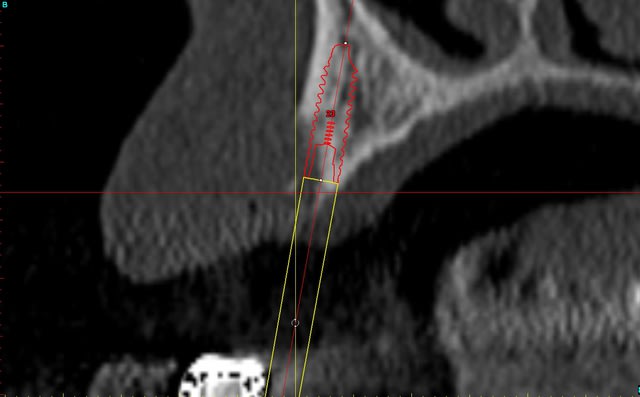

merci pour tes réponses, pour ma part (expérience avec plus de 600 implantation immédiate) je ne pense pas qu'il va y avoir une résorption, car pas de lambeau et tu n'as pas mis de trop grande pression sur l'os buccal.Un exemple ci dessous implantation ( 4 semaines après extraction) avec un 4.5 que (oui déjà mis dans un autre post).J'ai d'autres exemples similaires en extraction implantation immédiate mais avec des implants 3.5mm.Si l'espace entre l'implant et l'os buccal est plus grand que 1mm j'ajoute du collagène et de l'acide hyaluronique pour accélérer la régénération.

dernière radio à un an après cémentation de la couronne.

Ce qui est non négligeable est d'avoir une stabilité primaire d'un minimum de 35Ncm et pas plus de 70Ncm.

un cas récent os vestibulaire très fin.